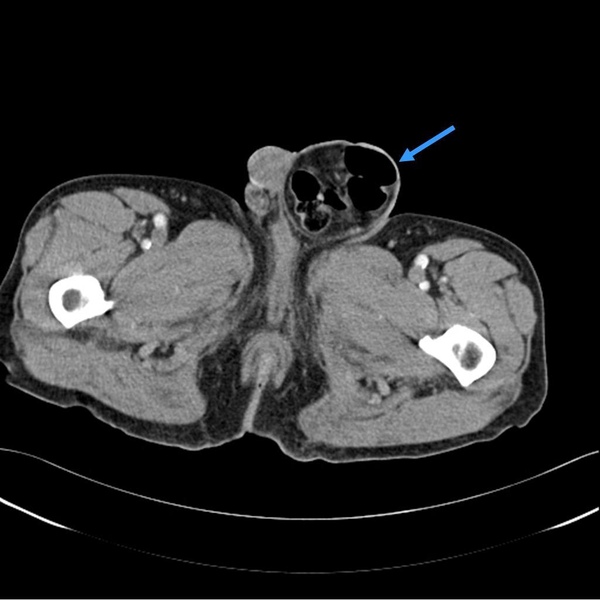

上圖是左側腹股溝疝氣,藍色箭頭處可以見到一些空氣,代表有小腸落入疝氣囊中。這種情況會讓腸道不順,脹氣,時好時壞。有那麼一天可能成為嵌頓型疝氣,那是相當緊急,需要快快處理。